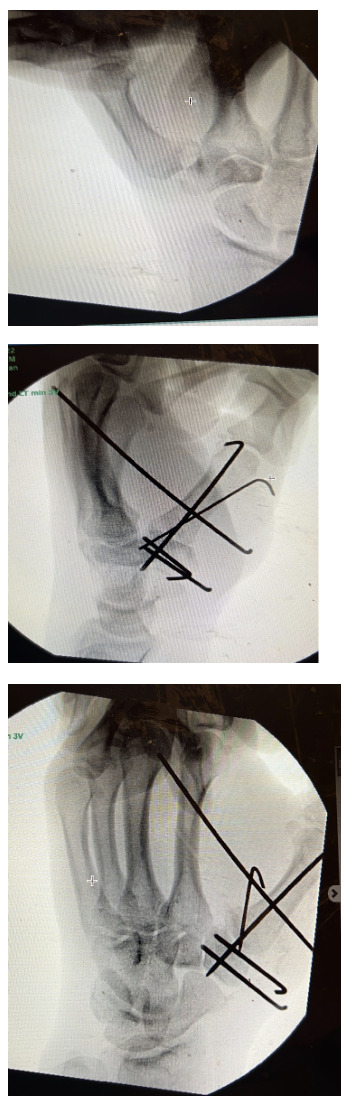

On physical exam, there was swelling over the wrist and the first carpometacarpal joint. There was crepitus and a gross dislocation of the trapezium over the first metacarpal. When the thumb was stabilized, EPL, FPL, middle finger flexion and extension and intrinsic muscles of the hand were all intact. Pulses and sensation were normal. Left arm was put in a short arm thumb spica splint, and CT of the wrist was ordered, showing a Bennett fracture as well as a trapezium comminuted fracture with dislocation of the thumb metacarpal. Images of the CT are shown in Fig.1 below. We decided to proceed with closed reduction and percutaneous pinning with possible open reduction and internal fixation.

Multiple 1.1 joysticks were used to obtain a near anatomical closed reduction. Then, multiple K-wires size 1.6 and 1.1 were used to secure and fix the trapezium fracture as well as the carpometacarpal dislocation through a wire spanning the thumb metacarpal bone and the trapezium, as well as another wire spanning the thumb and the index metacarpal bones as an added measure of safety to avoid a recurrent dislocation. Closed reduction of the Bennett fracture using a 1.1 K-wire was attempted with acceptable reduction obtained. Fluoroscopic images were satisfactory in multiple planes (Fig.2). Relaxing incisions were done around the K-wires and the pins were cut close to the skin and bent. A sterile dressing was applied followed by a combined sugar-tong and thumb spica splint. The patient’s arm was placed in an arm sling. The splint and pins were removed after 4 weeks.